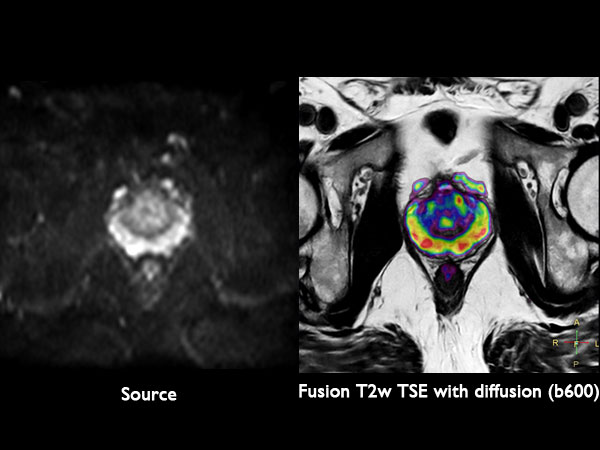

Diffusion